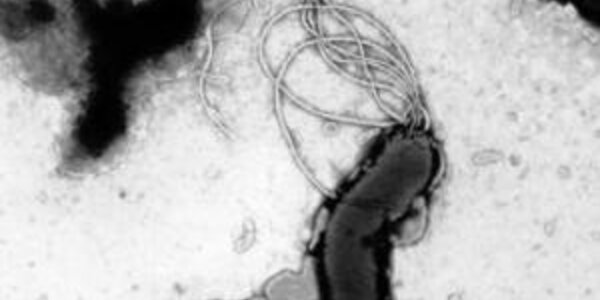

Prehistoric Origins Of Stomach Ulcers Uncovered

An international team of scientists has discovered that the ubiquitous bacteria that causes most painful stomach ulcers has been present in the human digestive system since modern man migrated from Africa over 60,000 years ago. The research, published online (7 February) by the journal Nature, not only furthers our understanding of a disease causing bacteria but also offers a new way to study the migration and diversification of early humans. A cell of H.pylori, a bacterial pathogen of the human stomach. The curved shape of the cell, and its bundle of flagella which enable it to wriggle…